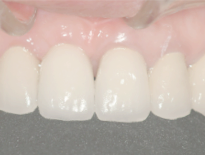

当歯科院症例写真

どの歯がインプラントかわかりません。

特に前歯のインプラントは審美性が

求められるので、

繊細な技術が必要です。